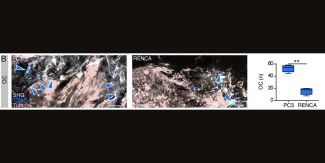

B. Analisi di immunofluorescenza; OC, TRAP; tumore, GFP; osso, SHG. È mostrata la quantificazione del numero di OC, boxplot con mediana; valori di P calcolati con test t di Student non appaiato a due code, p < 0,01 (**)

B. Immunofluorescence analysis; OC, TRAP; tumor, GFP; bone, SHG. A quantification of OC number is shown, boxplot with median; P values by unpaired two-tailed Student’s t test, p<0.01 (**).

Immunofluorescence analysis confirms that this process is associated with increased recruitment of osteoclasts (OC) by PC3. The same behavior is then recreated in the computational model, where osteoclasts are activated when tumors are located near the bone surface, leading to tissue resorption and replacement with tumor cells.